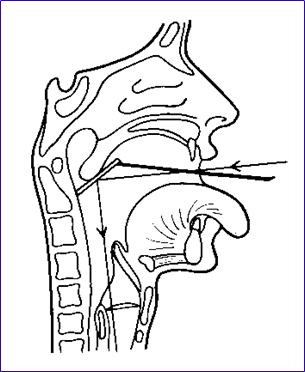

4.鼻咽镜(后鼻镜)检查

检查内容:

镜面向前向上:可见软腭的背面,鼻中隔后缘、后鼻孔、各鼻道及鼻甲的后段、鼻咽顶部;镜面向左向右转动:见咽鼓管咽口,咽鼓管隆突、咽隐窝等结构。

检查中注意鼻咽粘膜有无充血、粗糙、出血、浸润、溃疡、脓液、新生物及鼻咽两侧是否对称,以便早期发现鼻咽癌。